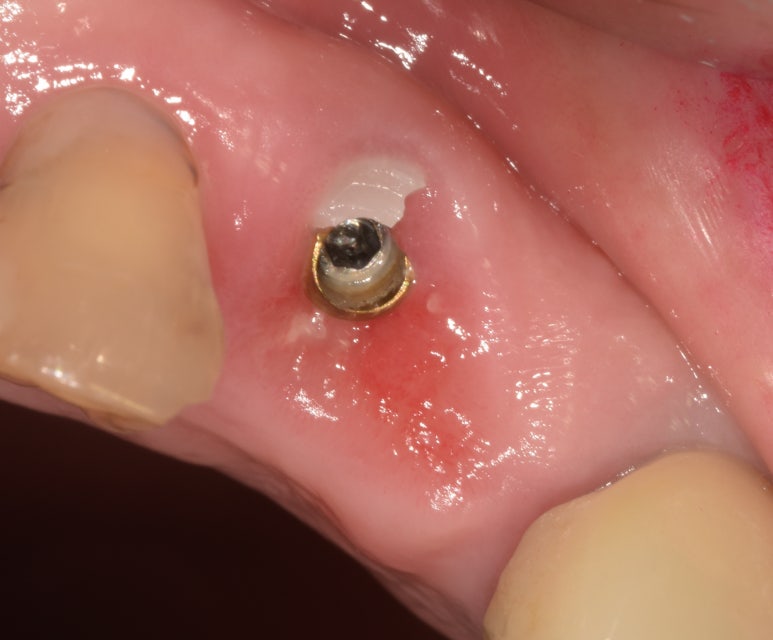

(좌) 앞니임플란트 시 지르코니아 어버트먼트를 장착한 상태

(우) 어버트먼트가 깨져 크라운과 함께 떨어진 상태

(좌) 2022-06-17 (우) 2023-02-04

지금 소개해드리는 환자분이 바로 이런 케이스였는데요.

앞니임플란트를 하셔서 금속으로 어버트먼트를 제작할 경우 색상이 비춰보일 수 있어

치아 색상과 유사한 지르코니아 어버트먼트를 하셨던 환자분입니다.

그런데 환자분께서 문에 부딪히는 바람에 이 어버트먼트가 깨져 크라운과 함께 탈락하고 말았습니다.

깨진 어버트먼트와 떨어진 크라운

일단 엑스레이를 촬영해보니 다행히도 임플란트 픽스처는 깨지지 않은 것으로 확인되었고,

픽스처가 뼈와 잘 유착되어 있는지 수치로 체크한 결과 이상이 없어서 1~2주 정도 지켜본 후

어버트먼트와 크라운만 다시 제작해 붙여드렸습니다.